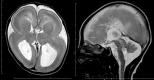

Neuronal migration disorders are human (or animal) diseases that result from a disruption in the normal movement of neurons from their original birth site to their final destination during early development. As a consequence, the neurons remain somewhere along their migratory route, their location depending on the pathological mechanism and its severity. The neurons form characteristic abnormalities, which are morphologically classified into several types, such as lissencephaly, heterotopia, and cobblestone dysplasia. Polymicrogyria is classified as a group of malformations that appear secondary to post-migration development; however, recent findings of the underlying molecular mechanisms reveal overlapping processes in the neuronal migration and post-migration development stages. Mutations of many genes are involved in neuronal migration disorders, such as LIS1 and DCX in classical lissencephaly spectrum, TUBA1A in microlissencephaly with agenesis of the corpus callosum, and RELN and VLDLR in lissencephaly with cerebellar hypoplasia. ARX is of particular interest from basic and clinical perspectives because it is critically involved in tangential migration of GABAergic interneurons in the forebrain and its mutations cause a variety of phenotypes ranging from hydranencephaly or lissencephaly to early-onset epileptic encephalopathies, including Ohtahara syndrome and infantile spasms or intellectual disability with no brain malformations. The recent advances in gene and genome analysis technologies will enable the genetic basis of neuronal migration disorders to be unraveled, which, in turn, will facilitate genotype-phenotype correlations to be determined.